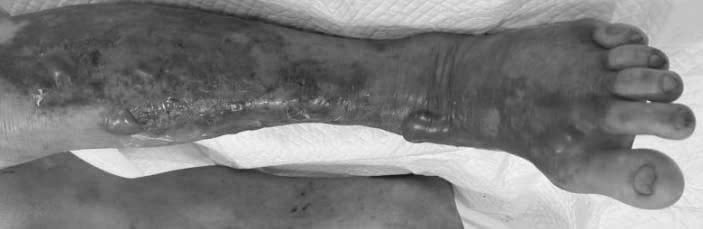

Cụ thể, người bệnh T. (59 tuổi), là ngư dân nhập viện Bệnh viện TWQĐ 108 trong tình trạng hoại tử da cẳng chân trái, lan nhanh đến đùi và bẹn, kèm tổn thương gan và thận.

Bệnh tiến triển cấp tính chỉ trong 1 đến 2 ngày, khiến bệnh nhân từng hôn mê và rơi vào tình trạng nguy kịch.

Bệnh dễ mắc ở người có bệnh nền như tiểu đường, xơ gan, gút, suy giảm miễn dịch hoặc đang điều trị ung thư, ghép tạng. Khi nhiễm khuẩn, trong 12 đến 48 giờ, vùng da bị đỏ, sưng, đau, xuất hiện bóng nước tím/đen hoặc hoại tử.

Đặc biệt, nếu không điều trị kịp thời, nhiễm trùng có thể lan rộng, gây viêm cân mạc hoại tử, sốc nhiễm khuẩn, suy đa tạng và nguy cơ tử vong cao.